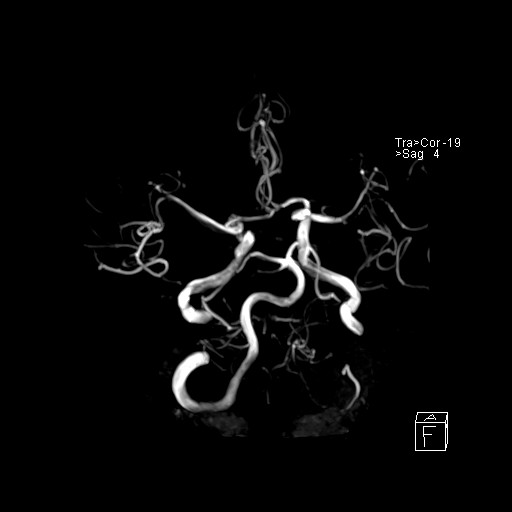

239716 - VILLANUEVA, WILLIAM A. - Number 2 |

239716 - VILLANUEVA, WILLIAM A. - Number 2 |